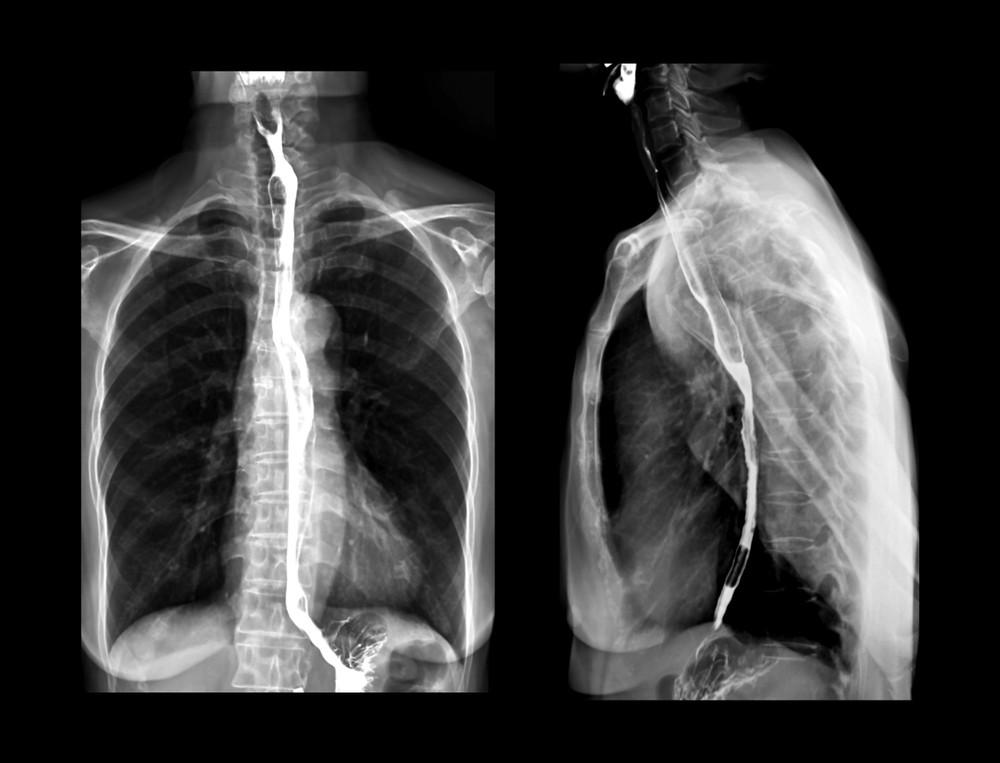

Barium swallow adalah tes pencitraan untuk memeriksa masalah pada saluran pencernaan bagian atas. Tes ini menggunakan jenis sinar X khusus yang disebut fluoroskopi yang dapat menunjukkan organ dalam bergerak secara real time.

Barium swallow atau tes fluoroskopi adalah pemeriksaan rontgen khusus untuk mengetahui kondisi saluran pencernaan atas. Saluran ini terdiri atas mulut, faring (bagian belakang tenggorokan), kerongkongan, lambung, dan duodenum (bagian pertama dari usus halus).

Barium merupakan cairan berwarna putih yang digunakan dalam pemeriksaan ini. Saat melewati saluran pencernaan, barium akan melapisi kerongkongan, lambung, atau usus sehingga organ-organ ini dapat terlihat pada pemeriksaan rontgen.

Radiolog kemudian melanjutkan rontgen atau fluoroskopi untuk melihat pergerakan barium dalam tubuh Anda.